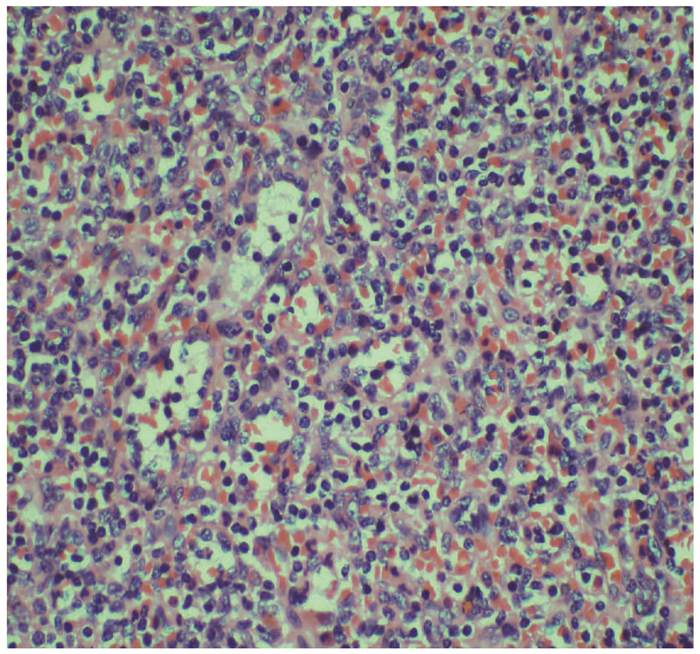

胰腺内副脾误诊为胰腺神经内分泌肿瘤1例报告

夏旭翔, 吕国悦, 仇晓桐, 邱伟

2022, 38(2): 436-438. DOI: 10.3969/j.issn.1001-5256.2022.02.036

摘要(1186) HTML (864) PDF (2885KB)(59)

摘要: